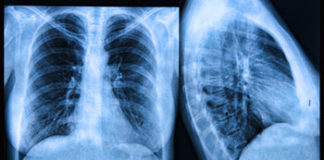

‘Rak više nije smrtonosna bolest, sad je kronična, mnogi s time žive’ Rad s onkološkim bolesnicima vodeća je tema Petog međunarodnog kongresa medicine usmjerene prema osobi, koji je u...